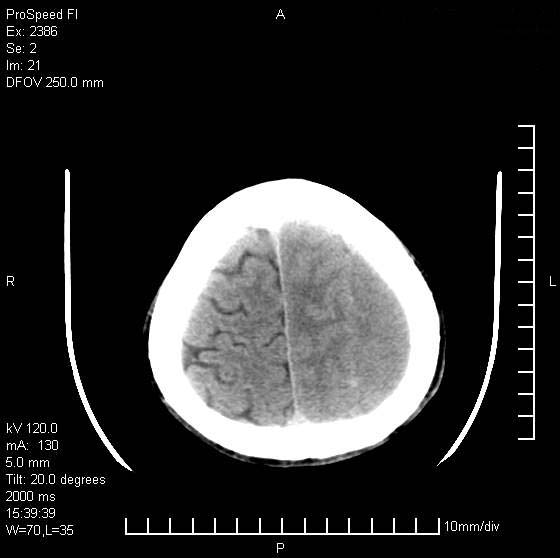

以下是引用天南地北在2007-9-19 18:43:00的发言:[br]典型慢性硬膜外血肿[br][br][本贴已被 天南地北 于 2007-9-19 18:44:11 修改过]

以下是引用曼一拍在2007-9-20 11:06:00的发言:[br]支持慢性硬膜下血肿.[br]慢性硬膜下积液:血肿有包膜,ct值稍高于脑脊液,增强可有染色。不典型者血肿可多呈梭形.是硬脑膜与蛛网膜之间的潜在腔隙内的血肿。[br]鉴别:[br]1\\硬膜外血肿:是颅脑外伤后脑膜或板障内血管破裂,血液在颅骨与硬膜之间积聚所致.通常是脑膜动脉破裂,也可因静脉窦破裂或颅骨的板障静脉出血,发生于外伤的着力部,常与颅骨骨折并存。脑膜动脉出血则急,若是板障静脉出血在则可有慢性。[br]2\\硬膜下积液:(硬膜下水瘤)[br]是由于蛛网膜破裂,脑脊液经蛛网膜破口进入硬膜下腔不能回流。或水肿阻塞而形成。[br]ct表现:颅骨内板下方新月形低密度区近似脑脊液密度;占位效应清,周围无脑水肿。[br]